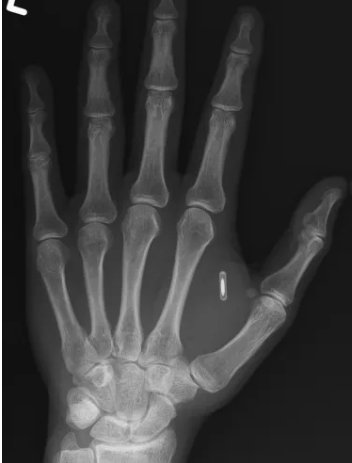

Технологічні експерименти нерідко стають частиною перформансів, особливо коли йдеться про сучасну магію. Проте інколи інновації можуть обернутися несподіваними труднощами. Саме це сталося з фокусником Цзи Тен Ваном, який імплантував у руку RFID-чіп, але згодом втратив до нього доступ, оскільки забув встановлений пароль.

За інформацією, поширеною Ваном, він встановив імплант для того, щоб під час виступів безконтактно активувати певні функції на смартфонах глядачів. Ідея звучала сучасно та ефектно, однак на практиці виявилася не такою простою.

Коли артист спробував переписати інформацію втретє, він зіткнувся з несподіваною проблемою — пароль, який він встановив кілька років тому, був повністю забутий.

Зіткнувшись із блокуванням, фокусник звернувся по допомогу до друзів, які працюють у сфері технологій. За їхніми оцінками, імплантований RFID-чіп є дуже простим пристроєм, що працює за базовими принципами безпеки.

На відміну від сучасних смартфонів чи захищених сховищ, він не підтримує відновлення пароля, зміну ключів доступу чи дистанційне скидання налаштувань. Якщо пароль втрачено, «обійти» його практично неможливо.